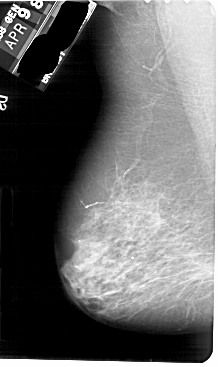

A_1700_1.LEFT_MLO

LEFT_MLO LINES 5491 PIXELS_PER_LINE 3256 BITS_PER_PIXEL 12 RESOLUTION 43.5 NON_OVERLAY